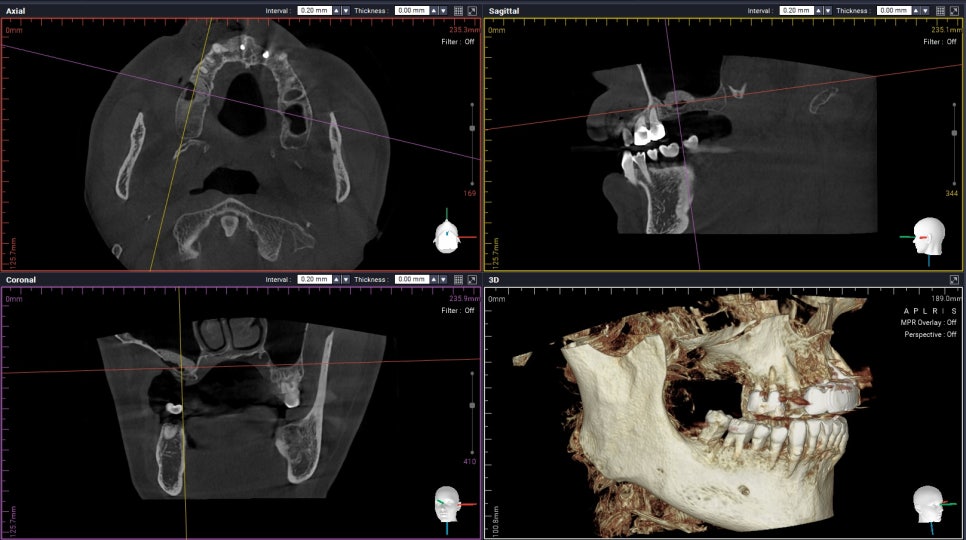

Progress CBCT Tooth No. 2,3

모든 진료에 너무나도 꼼꼼한

Dr. Kim은

상악동 거상술 중간에

이렇게 3D CT를 찍어

상악동막이 찢기지는 않았는지,

뼈이식 양과 높이는 제대로 올라가는지

꼭 체크합니다. :)